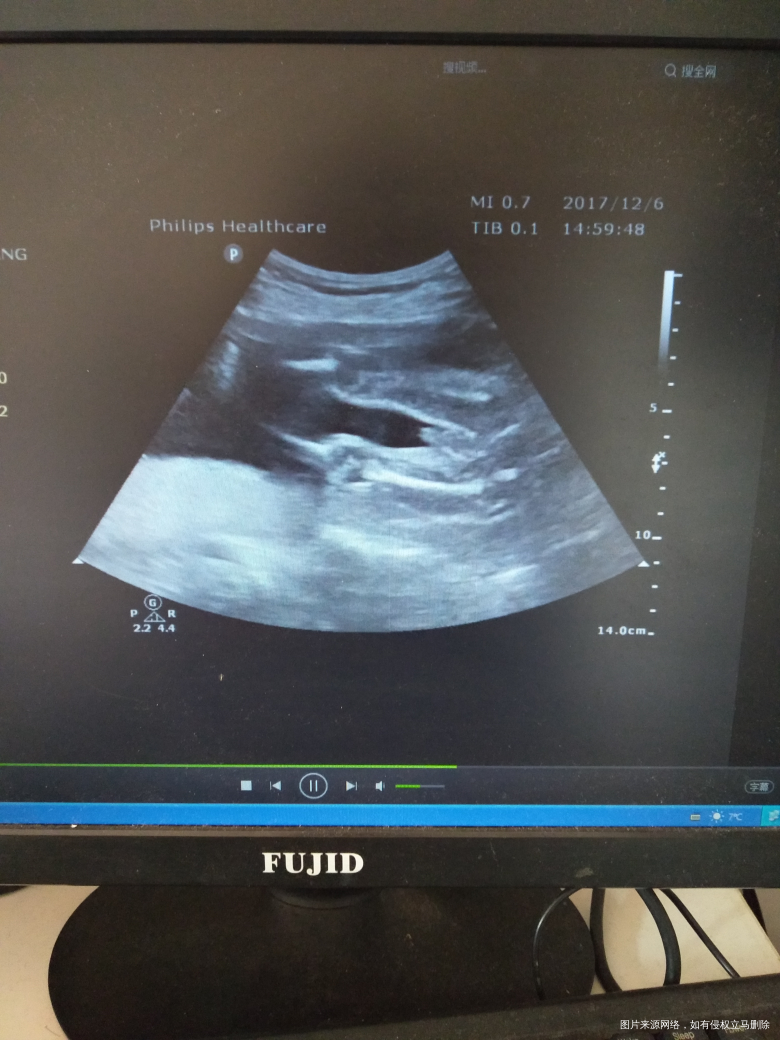

我也不知道,这种问题。该不该问

,但是我真的好想知道自己又看不懂。

这个彩超没法看是男孩还是女孩

若曦 回复 张文娟:为什么呢,这不是最直观的图片吗

你好,这个彩超没法看男孩女孩,只要胎儿健康就好。

你好,做B超的医师在检查的过程中是可以看到的,单纯的图片是看不到的。

你好,一般彩超图片不会让你看出男女,有时候脐带干扰的。